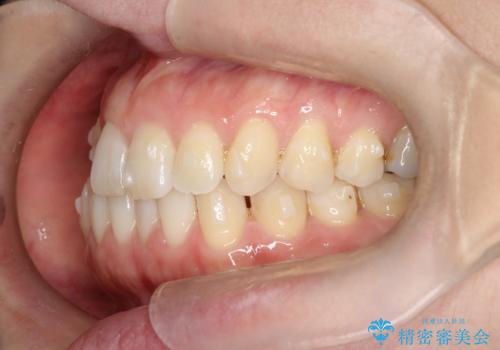

- 右上の前から2番目と3番目の歯が内側に引っ込んでしまっているのを主訴に来院されました。

右上の2番目と3番目のはが前後反対にかんでしまっている状態でした。

インビザラインにて治療することとしました。

内側に引っ込んでいる歯も、インビザラインにてしっかり外側に動かすことができます。